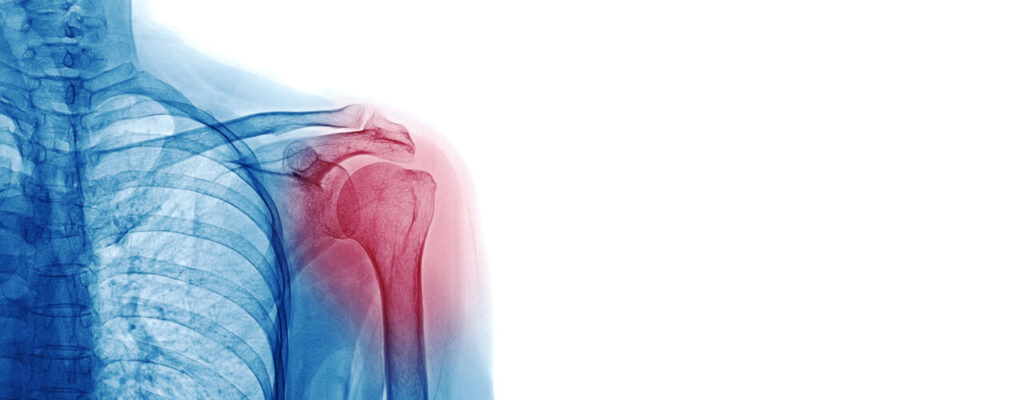

Physical Therapy for Shoulder Injury Recovery: What to Expect

Shoulder injuries can be frustrating, limiting your ability to perform everyday activities or enjoy your favorite hobbies. From minor strains to more serious conditions, shoulder pain often requires a comprehensive approach to recovery. Physical therapy offers a proven path to healing, focusing on improving mobility, building strength, and restoring function. At ProResults Physical Therapy, our therapists guide patients through every stage of shoulder injury recovery, tailoring care to individual needs and goals.